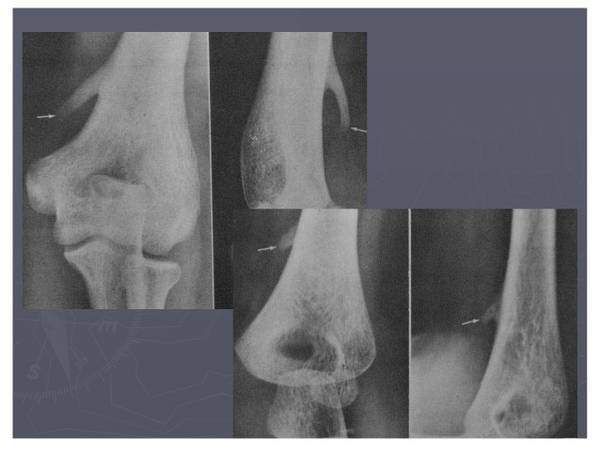

常见异常副骨或籽骨

谢谢张老师的讲解。非常丰富。一张X线片上显示骰骨外侧籽骨,和同事争论到底是维扎里骨还是腓骨肌籽骨,但可查的资料太少了,所以求助于张老师。给你添麻烦了,再次感谢。